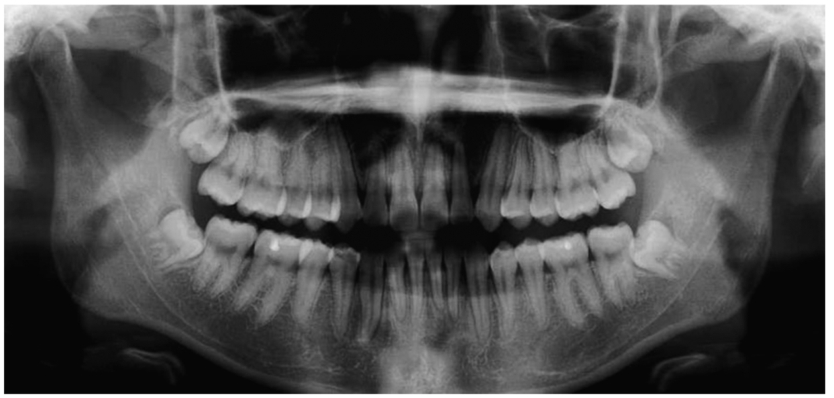

图1 全景片全景片显示下颌骨的组成